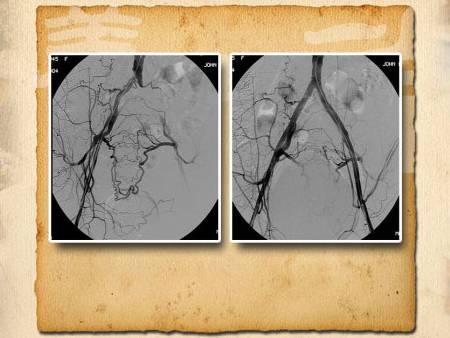

看看電視劇泡泡腳,是很多老年人的習(xí)慣。但是并不是所有的人都適合泡腳,比如下肢動脈血管有堵塞的人。另外,高血壓、心臟病的患者不要長時(shí)間的用溫度過高的水泡腳,對身體也不好。敬請收看由中日友好醫(yī)院心外科主任劉鵬教授主講的《從血管看壽命—2》。

腿部血管堵塞,可能會在走路時(shí)候,走著走著腿就感覺疼、沉,要停下來休息休息。另外,如果發(fā)現(xiàn)自己的趾甲增厚、腿毛變少,也可能是腿部血管堵塞的表現(xiàn)。自己的感覺只能是初步判斷,那去醫(yī)院做什么檢查能發(fā)現(xiàn)自己的腿部血管有沒有堵塞呢?更多具體內(nèi)容請收看本期節(jié)目。

足背動脈很好找,在節(jié)目中也給大家介紹過多次。(位置如圖)足背動脈摸不到或者搏動很弱的人可能就是足背動脈有堵塞了。那這條動脈堵了,腿部供血就該有問題了吧?是不是就要去醫(yī)院做手術(shù)了呢?也不一定。因?yàn)樵谖覀兺壬线€有其他動脈血管存在,一條堵了,還有其他的血管能彌補(bǔ)已經(jīng)堵塞的足背動脈的不足,那還能摸摸哪兒自查其他血管好不好呢?更多具體內(nèi)容請收看本期節(jié)目。